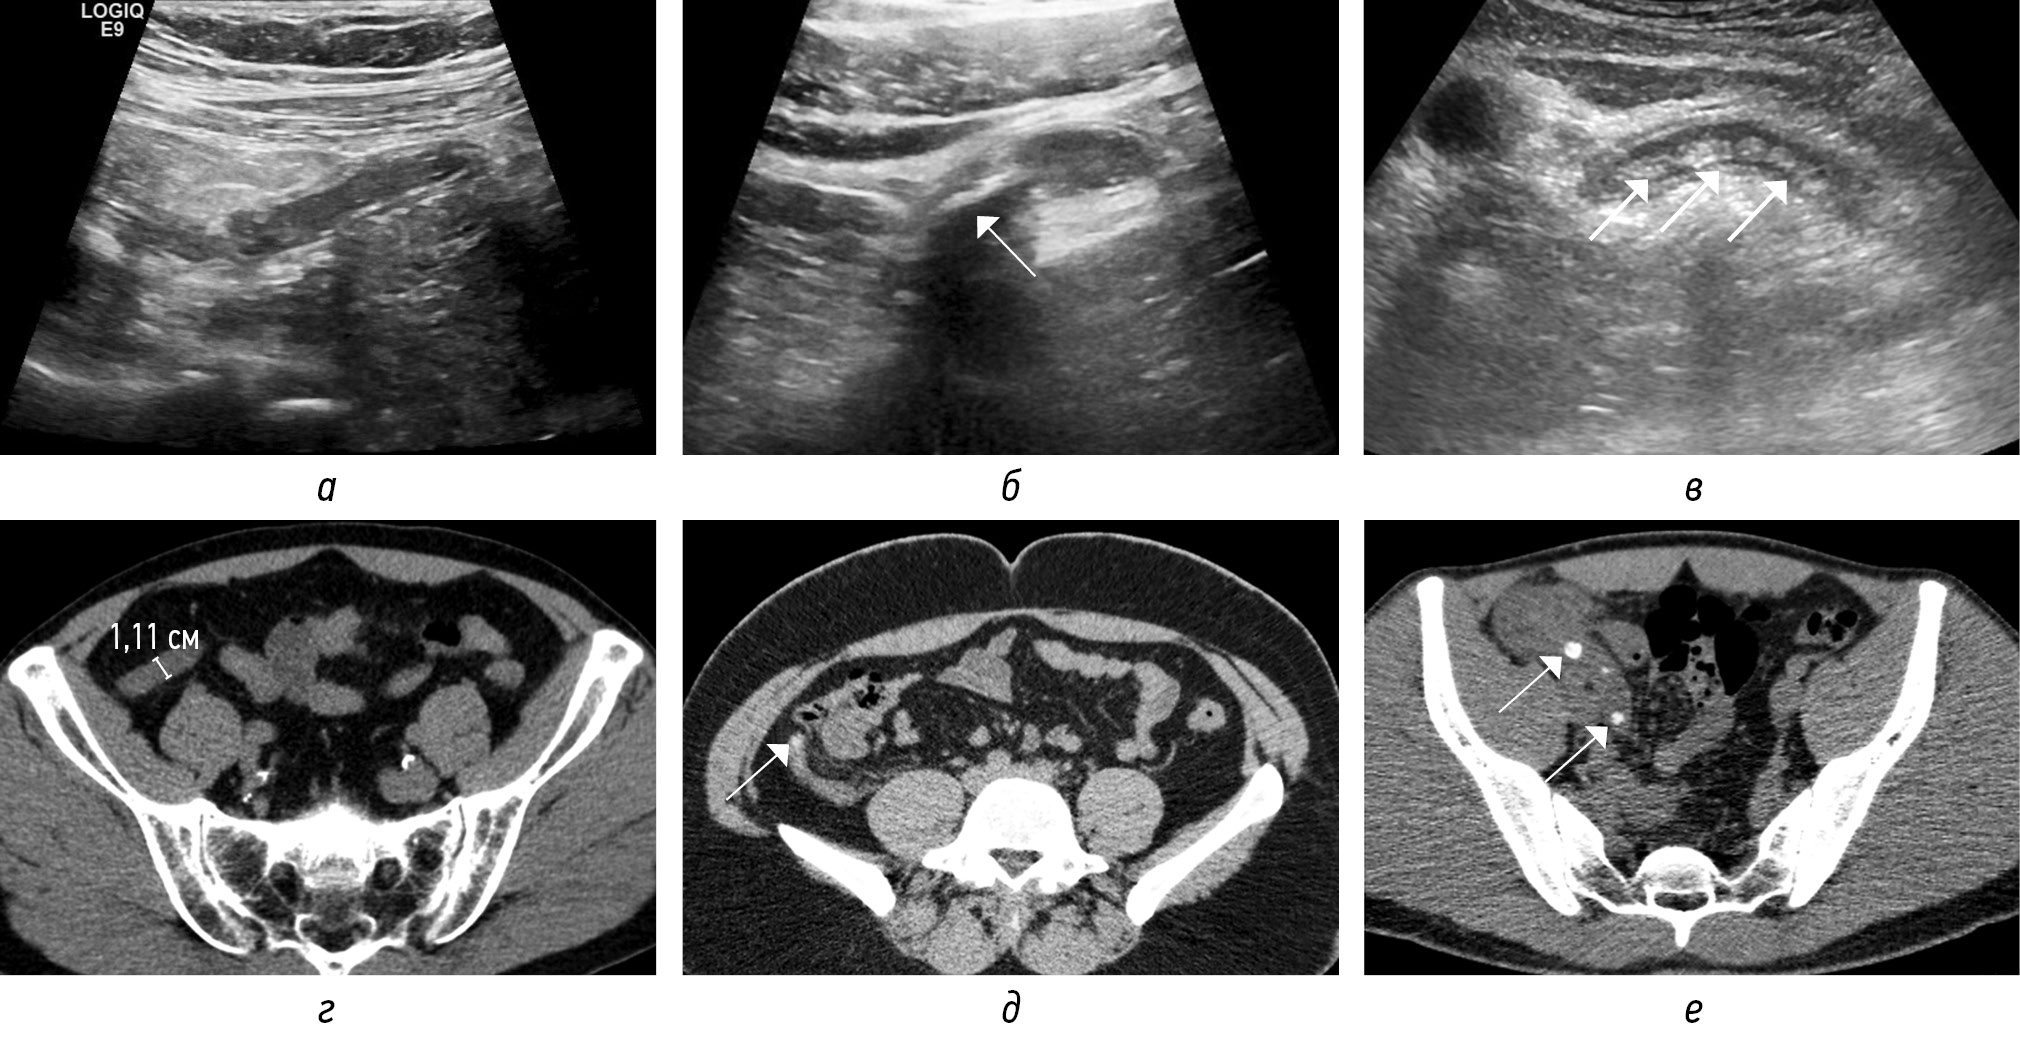

При пограничном ОА (тип 1а), при поражении только слизистой и подслизистой оболочек, незначительно увеличивается диаметр аппендикса (6–8 мм) с сохранением слоев, без косвенных признаков воспаления (рис. 13, а, б). При неосложненном флегмонозном ОА (тип 1б) слои аппендикса сохранены, размыты, диаметр увеличен (обычно >8 мм), гиперваскуляризация/усиление стенок, отсутствие или минимальное количество внепросветной жидкости, умеренная гиперэхогенность/исчерченность периаппендикулярной жировой клетчатки (рис. 14, а, б).

Рис. 13. Сонограммы в В-режиме (а — продольный скан аппендикса; б — поперечный скан аппендикса). Воспаленный аппендикс (стрелки) с четко дифференцируемыми стенками, содержимым в просвете

Fig. 13. B-mode sonograms (а — longitudinal scan of the appendix; б — transverse scan of the appendix). Inflamed appendix (arrows) with clearly differentiable walls, contents in the lumen

Рис. 14. КТ-изображения во фронтальной плоскости в нативную (а) и постконтрастную (б) фазы: аппендикулярный отросток (стрелки) увеличен (12 мм), стенки усиливаются, умеренная исчерченность периаппендикулярной жировой клетчатки

Fig. 14. CT images in the frontal plane in the native phase (а) and post-contrast phase (б): the appendicular process (arrows) is enlarged (12 mm), the walls are strengthened, moderate striation of periappendicular adipose tissue

Осложненный ОА характеризуется либо перфорацией (тип 3), либо ожидаемой перфорацией (тип 2). Ключевым визуализационным признаком осложненного ОА являются выраженные изменения периаппендикулярной ткани: гиперэхогенность на УЗИ или тяжистое уплотнение на КТ. Выраженная, но все еще локализованная периаппендикулярная жидкость или обструкция наблюдается при тяжелом флегмонозном ОА (тип 2а). Гангренозный ОА (тип 2б) характеризуется наличием интрамурального газа и/или потерей эхогенного подслизистого слоя. Некоторые авторы классифицируют тяжелый флегмонозный ОА (тип 2а) и даже гангренозный ОА (тип 2б) как неосложненный ОА, предположительно потому, что они определяют осложнения исключительно по наличию перфорации. Нoffmann J.C. et al. предлагают классифицировать эти типы как осложненные ОА в соответствии с консенсусным заявлением Европейской ассоциации эндоскопической хирургии, опираясь на многочисленные исследования, показавших, что аппендиколит с обструкцией (рис. 15, а–г), выраженное периаппендикулярное воспаление и гангрена указывают на неизбежную перфорацию [2]. Перфорация может быть прикрытой с абсцессом (тип 3а) или неприкрытой со свободной жидкостью, газом и гноем в брюшной полости (тип 3б). Иногда можно обнаружить псевдообразование аппендикса за счет вовлечения в воспалительный процесс прилежащих петлей тонкой или толстой кишки, что также представляет собой локализованную форму перфорации, т. е. тип 3а.

Рис. 15. КТ-томограммы (а) в трех плоскостях на уровне аппендикса с наличием в нижней трети аппендиколита (на изображениях соответствует точке пересечения секущих линий) с обструкцией просвета и расширением просвета выше препятствия, с отеком периаппендикулярной жировой клетчатки. Сонограммы (б–г) в В-режиме демонстрируют аппендиколит, участки аппендикса без расширения просвета и мешковидное расширение выше препятствия (стрелка)

Fig. 15. CT-tomograms (a) in three planes at the level of the appendix with the presence of appendicolitis in the lower third (in the images corresponds to the intersection point of the secant lines) with obstruction of the lumen and expansion of the lumen above the obstacle, with swelling of the periappendicular fatty tissue. Sonograms (б–г) in B-mode demonstrate appendicolitis and areas of the appendix without expansion of the lumen and sac-like expansion above the obstacle (arrow)